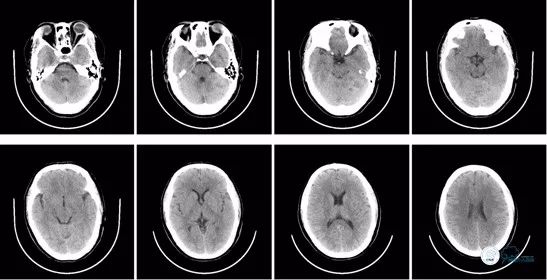

术后8小时头颅CT:

图13

术后即刻头颅CT:可见少量造影剂渗出,排除术后出血。

图11